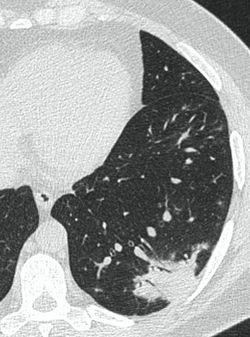

4.3. ЛУЧЕВАЯ ДИАГНОСТИКА COVID-19

Методы лучевой диагностики применяют для выявления COVID-19 пневмоний, их осложнений, дифференциальной диагностики с другими заболеваниями легких, а также для определения степени выраженности и динамики изменений, оценки эффективности проводимой терапии.

К методам лучевой диагностики патологии ОГК пациентов с предполагаемой/установленной COVID-19 пневмонией относят:

- Компьютерную томографию легких (КТ),

КТ имеет высокую чувствительность в выявлении изменений в легких, характерных для COVID-19. Применение КТ целесообразно для первичной оценки состояния ОГК у пациентов с тяжелыми прогрессирующими формами заболевания, а также для дифференциальной диагностики выявленных изменений и оценки динамики процесса. КТ позволяет выявить характерные изменения в легких у пациентов с COVID-19 еще до появления положительных лабораторных тестов на инфекцию с помощью МАНК. В то же время, КТ выявляет изменения легких у значительного числа пациентов с бессимптомной и легкой формами заболевания, которым не требуется госпитализация. Результаты КТ в этих случаях не влияют на тактику лечения и прогноз заболевания при наличии лабораторного подтверждения COVID-19. Поэтому массовое применение КТ для скрининга асимптомных и легких форм болезни не рекомендуется.

15. Рекомендации по формированию описаний и оценке изменений в легких и ОГК при имеющейся/подозреваемой пневмонии COVID-19 представлены в Приложении 1.